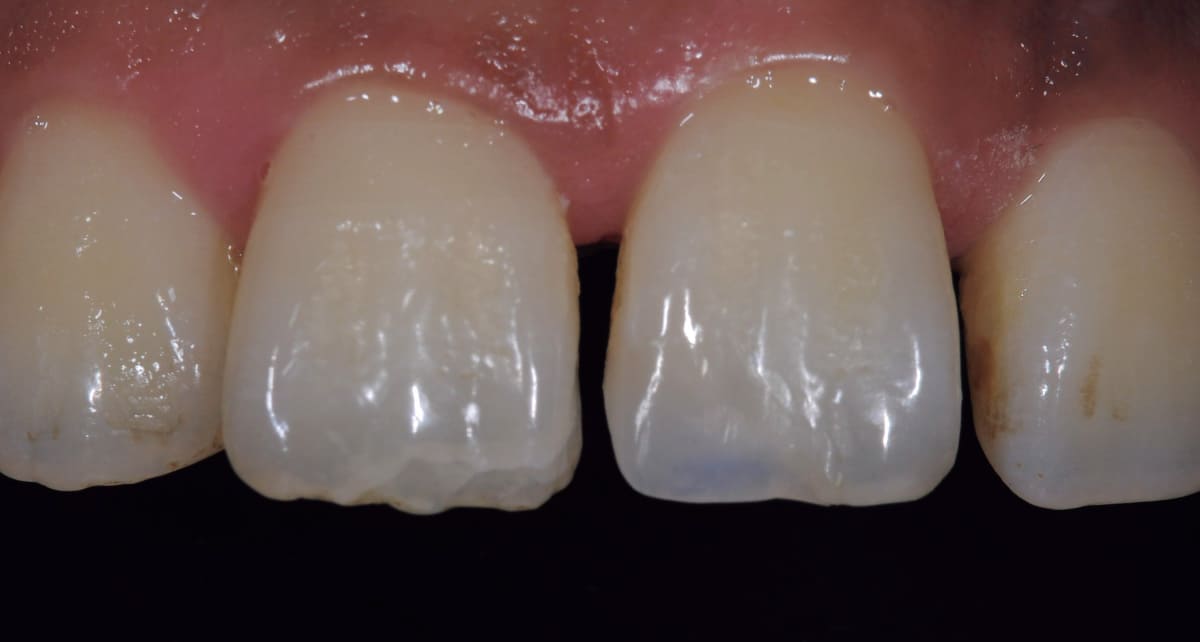

ダイレクトボンディング|ペースト状の材料を歯に盛り付けるだけ。

Before

After

むし歯や前歯の隙間、欠けた歯を修復する治療。セラミックとプラスチックの混合物であるレジンというペースト状の材料を直接歯に盛り付ける。クラウンのように型取りする必要もないので短期間で済み、歯を削る範囲も最小限。

【料金】3万円〜

【治療期間】1日〜2週間程度